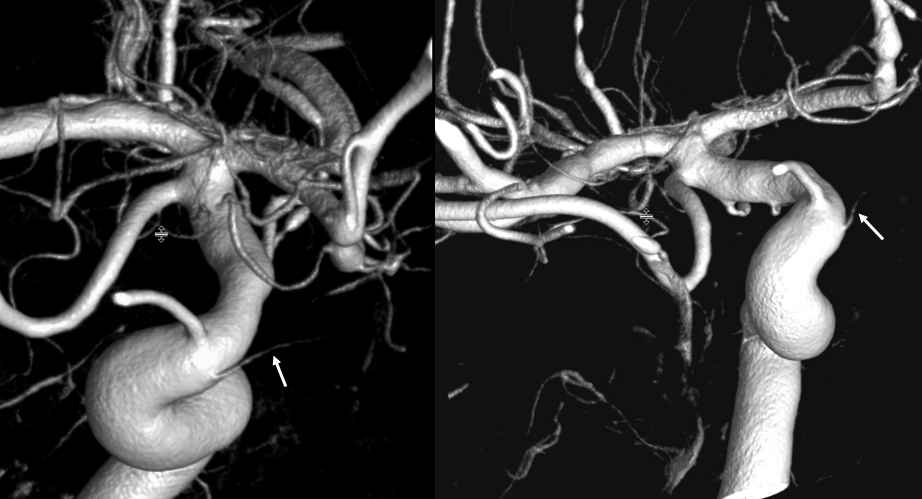

Posterior Pituitary Supply — MHT Balance

Excellent example of contralateral balance. On the left, there is a hypoplastic posterior hypophyseal network (part of MHT, arrowhead), and a prominent superior hypophyseal artery (associated with a small aneurysm). On the right, the opposite is true — large inferior hypophyseal arteries (dashed arrows) extending past midline due to contralateral hypoplasia, and a smaller superior hypophyseal, without aneurysm — not visible on these VRs, but seen on subsequent MIP images

MIP images — there is a small right superior hypophyseal artery present